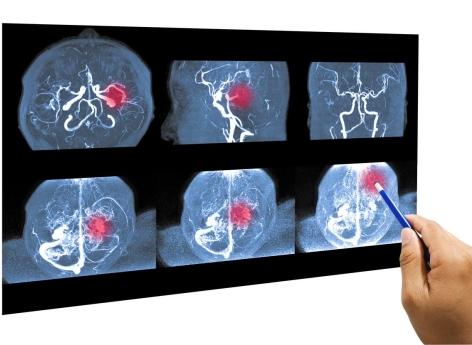

Les anévrismes cérébraux sont plus fréquents chez les personnes âgées de 30 à 60 ans et les femmes y sont plus sujettes que les hommes, selon le Manuel MSD. Ils peuvent être définis comme des dilatations focales des artères. Ces dilatations se caractérisent par une poche de sang qui grossit lentement au niveau de la paroi de l'artère et la fragilise. Quand il y a une rupture d’anévrisme, cela provoque une hémorragie interne qui peut être très grave, notamment quand il s’agit de l’artère cérébrale. D’après le Vidal, les anévrismes du cerveau sont responsables d’environ 10 % des accidents vasculaires cérébraux (AVC).

Il y a plusieurs facteurs de risque aux anévrismes cérébraux : l’âge, les antécédents familiaux, l’obésité, le diabète, l’hypertension artérielle, le tabagisme, l’alcoolisme chronique, l’excès de lipides (le cholestérol) dans le sang, un traumatisme crânien ou une lésion importante du thorax, certaines maladies infectieuses ou génétiques… Et, selon cette nouvelle recherche, le virus VIH, qui pourrait constituer un facteur de risque supplémentaire.